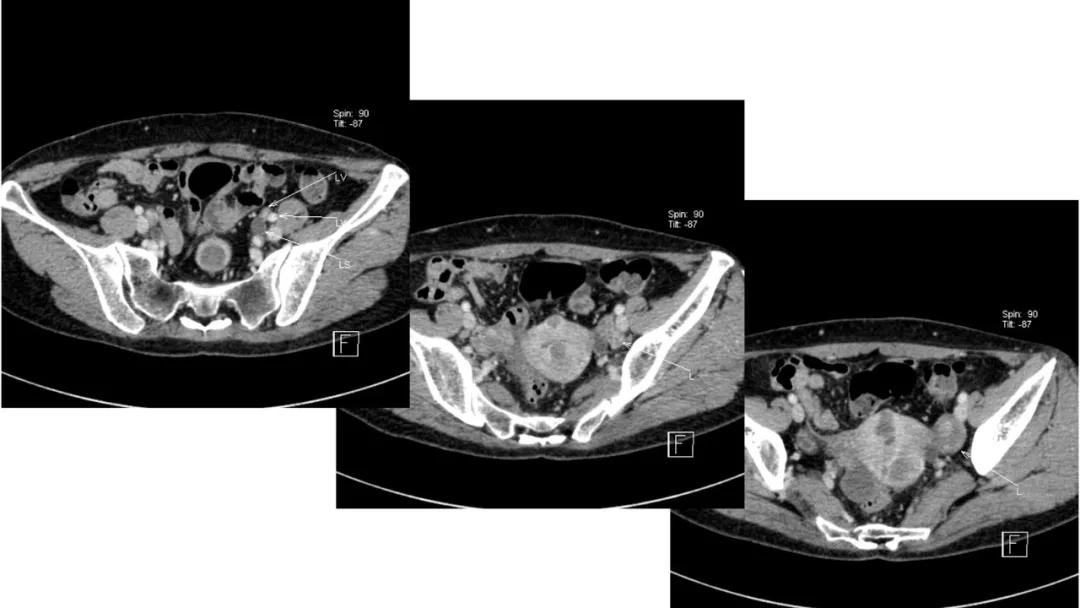

病例10

女,39 岁,体检发现盆腔肿块1月余

CA125:51U/ml

病理:左侧卵巢卵泡膜-纤维瘤